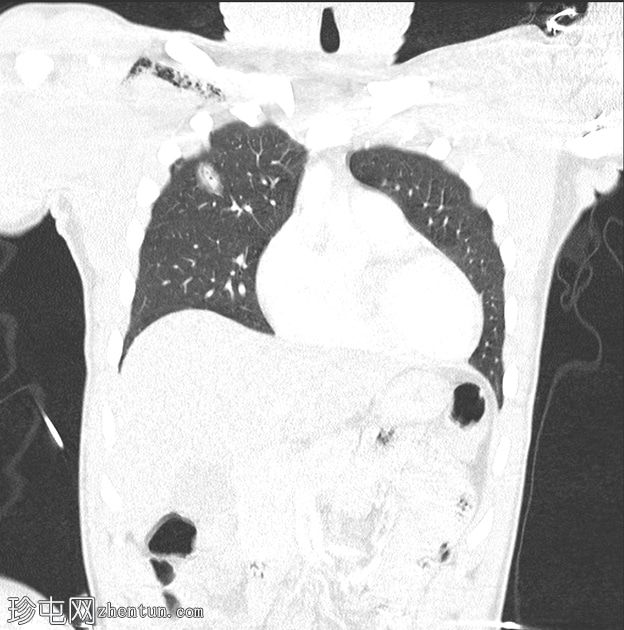

胸部

穿透伤

CT扫描

冠状面C+

动脉期

皮下气肿。右胸壁穿透伤,横穿右胸大肌,进入右前第三和第四肋骨之间的胸腔。右上叶49毫米裂伤,后方与水平裂隙相邻。伴有创伤性气囊和邻近毛玻璃影,与

肺

出血相符。右侧微小气胸。